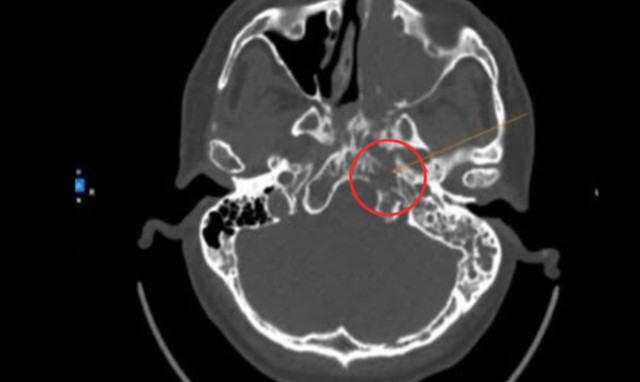

Kết quả chụp CT-scan ghi nhận tổn thương choán chỗ xoang hàm trái, lan vào hốc mũi qua lỗ thông xoang. Tổn thương lan vào lấp đầy xoang sàng, xoang trán và xoang bướm trái, phát triển về phía cửa mũi sau trái, lấp đầy vòm mũi họng hai bên. Tổn thương hủy xương clivus (xương nằm ở nền sọ) trái, tụ dịch khí chũm bào trái và quanh các xương con bên trái, theo dõi hạch góc hàm trái.

Hình ảnh CT-scan ghi nhận khối u hốc mũi che lấp vùng vòm họng người bệnh. Ảnh: BVCC